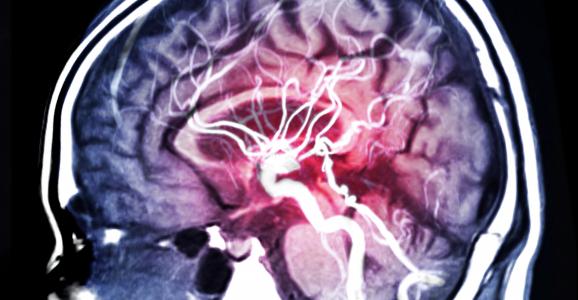

Un traitement antioxydant de l’AVC ischémique aigu pourrait retarder l'apparition de la maladie d'Alzheimer, conclut cette recherche d’une équipe de l’Université d’Oradea (Roumanie) dans la revue CNS & Neurological Disorders - Drug Targets. Un examen de la littérature qui présente l’AVC ischémique aigu comme le déclencheur, via une montée de stress oxydatif, d’une accélération subite du déclin cognitif.

Les chercheurs partent ici des preuves de plus en plus nombreuses de l'association de facteurs de risque vasculaires comme l'hypertension, les taux élevés de cholestérol ou le diabète avec l’incidence de troubles cognitifs et de la maladie d'Alzheimer. Il se trouve que ces facteurs augmentent fortement le risque d’AVC ischémique et que par ailleurs, un AVC incident double approximativement le risque de démence, en particulier en raison des pertes neuronales qui se produisent alors par nécrose ischémique et peuvent se prolonger jusqu'à 2 semaines après l’AVC.

Plusieurs études ont ainsi montré une augmentation constante du stress oxydatif après un AVC ischémique. Il existe au-delà un chevauchement considérable entre la pathogenèse induite par le stress oxydatif dans l’AVC ischémique et la maladie d'Alzheimer, dont le dysfonctionnement mitochondrial, la surcharge calcique des cellules, l'activation de différentes enzymes destructrices, l’expression de gènes « aberrants », l’induction de l'autophagie et l’activation de réponses inflammatoires.

Les chercheurs font donc l’hypothèse de l'implication progressive du stress oxydatif dans la genèse de la maladie d’Alzheimer et de son explosion, avec l’AVC, qui pourrait accélérer la pathogenèse de la démence et conduire à des troubles cognitifs cliniquement plus évidents. Si cette hypothèse était prouvée, le recours à un traitement antioxydant en cas d'AVC ischémique aigu permettrait de retarder, de quelques années, le développement des troubles cognitifs associés.